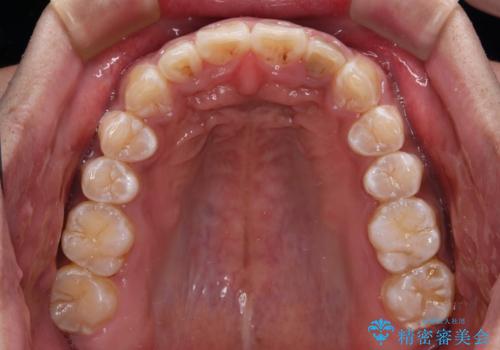

- 深く咬みこみ、前に飛び出した上顎前歯を気にして来院された患者様です。

口元の突出感はあまりありませんでしたが、上顎歯列が全体的に前方にあり、更には下顎歯列が深く咬みこんでいるために、上顎前歯が前方に突出している状態でした。

正面や横から見た印象が同じで用であっても、奥歯の咬み合わせが理想的であるかどうかによって、治療の難易度は大きく異なります。

こちらの方も難易度のやや高い状態で、2年以上の期間が予想されましたが、想定通りの2年強で治療を終えることができました。